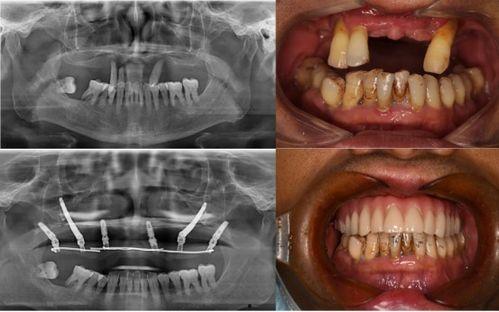

据患者们反映,他们在种植牙的过程中,遇到了种种问题。有的患者表示,医生在手术过程中操作不规范,导致种植牙失败;有的患者则抱怨,术后恢复期过长,而且效果并不理想。更有甚者,竟然出现了种植牙植入后,牙槽骨吸收的情况。

这起事件也引起了相关部门的关注。据知情人士透露,当地卫生部门已经介入调查,对这家口腔医院进行了全面检查。检查结果显示,这家医院在种植牙过程中确实存在一些不规范的操作。目前,相关部门已经对该医院进行了处罚,并要求其立即整改。

对于这起事件,口腔医学专家也给出了自己的看法。他们认为,种植牙是一项高风险的手术,需要医生具备丰富的经验和专业的技术。而这家口腔医院在种植牙过程中出现的问题,反映出我国口腔医疗行业在规范化、专业化方面还存在不少问题。